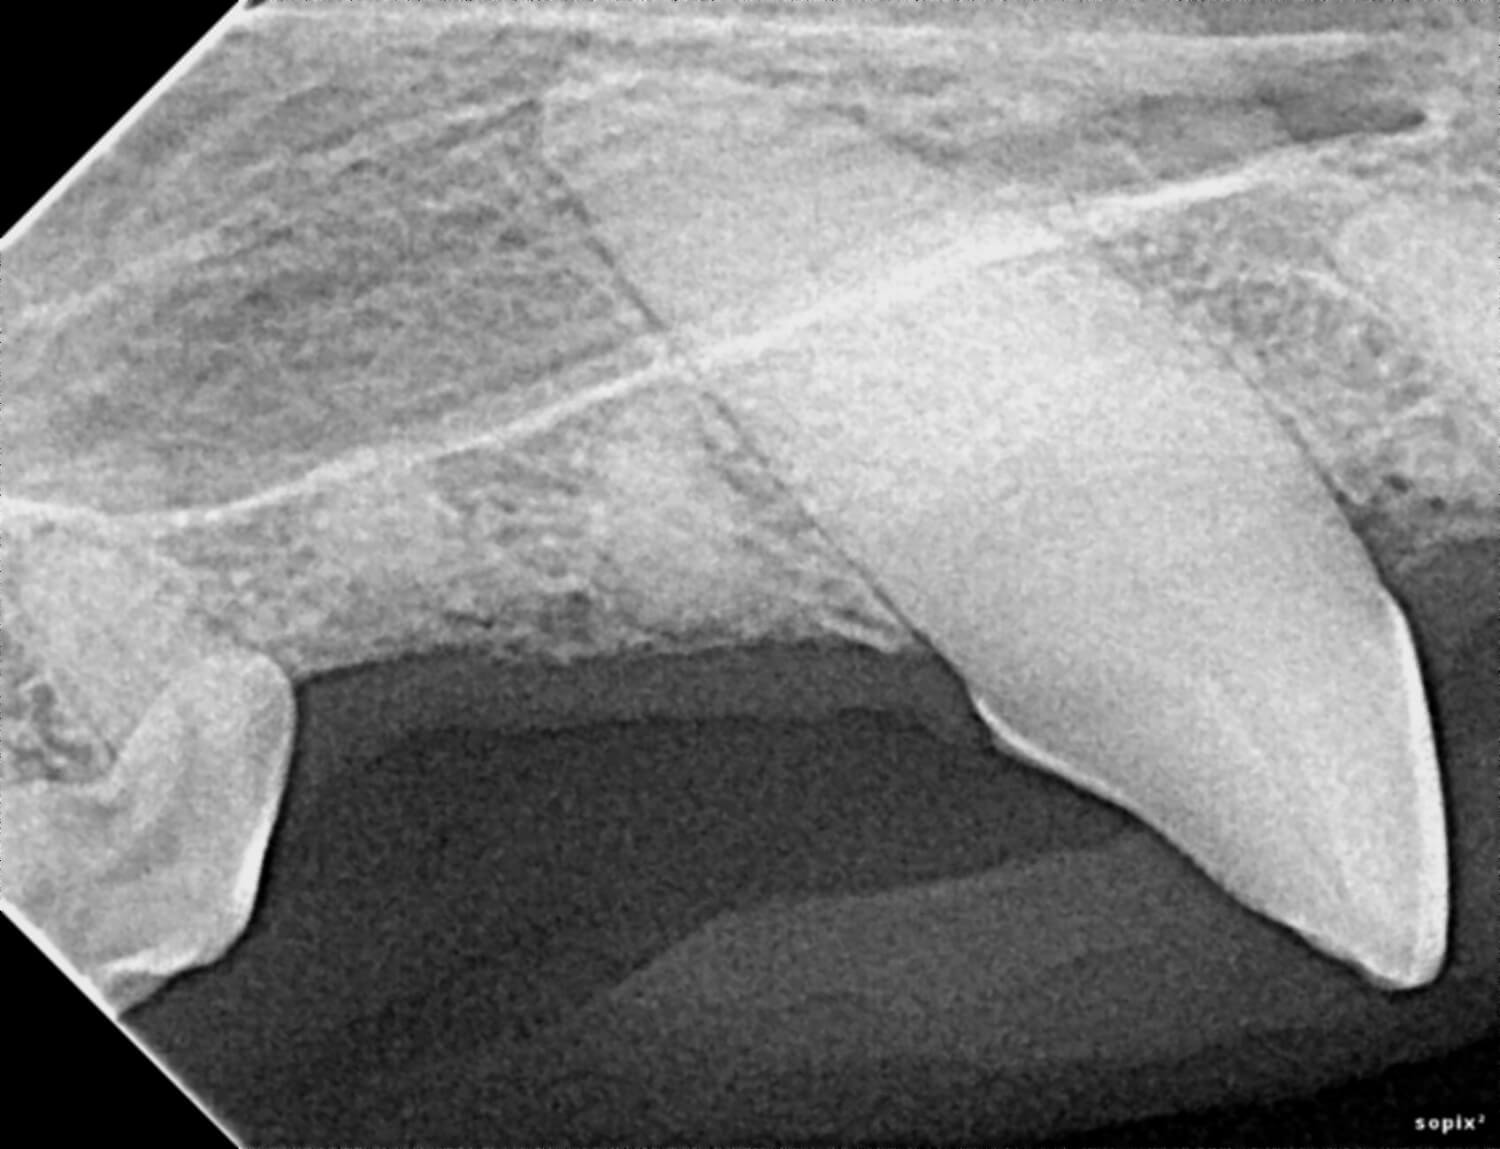

Digital radiology is a state-of-the-art imaging technique used to produce highly detailed X-ray images of your pet’s teeth, mouth, and jaw. This technology replaces traditional film X-rays; it provides instant results and clearer images, which lead to faster, more accurate diagnoses.

Our veterinarians use digital radiology to detect conditions such as tooth root abscesses, oral tumors, jaw fractures and hidden dental and periodontal issues. Early diagnosis enables timely treatment, reducing pain and preventing advanced dental complications.

We utilize state-of-the-art digital X-ray equipment to capture detailed images in seconds. The images appear instantly on our monitors, allowing our veterinarians to review and interpret results right away. This technology reduces your pet’s radiation exposure compared to traditional film.

Digital radiology plays a vital role in preventive health and advanced diagnosis for pets. Dental and oral conditions are often hidden below the gumline, where physical exams cannot detect them.

This imaging can reveal issues such as periodontal disease, infections, tooth resorption, and bone loss before they cause noticeable pain or lasting damage. Prompt diagnosis allows our team to provide targeted treatments that keep your pet comfortable and healthy.